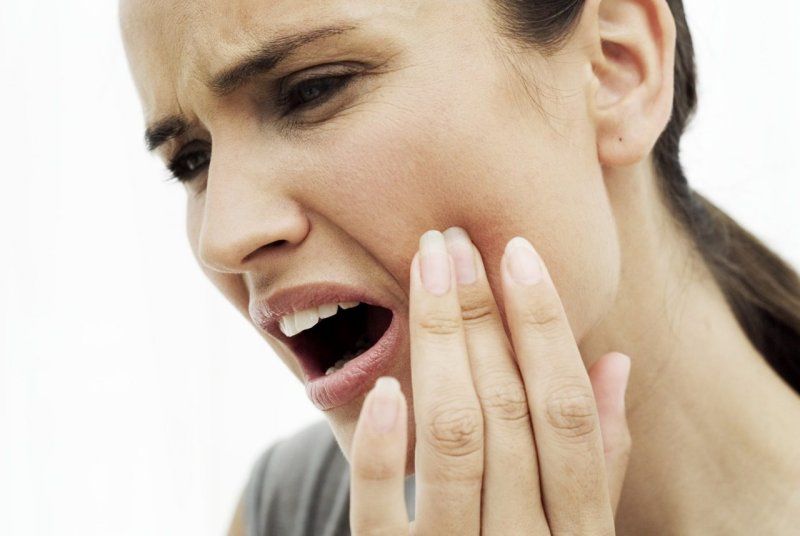

3. Đau Đớn và Khó Chịu

Một răng sâu không được nhổ có thể gây ra cơn đau liên tục và dữ dội. Cơn đau này không chỉ làm giảm chất lượng cuộc sống mà còn có thể ảnh hưởng đến tâm trạng và khả năng làm việc của bạn. Việc này có thể làm giảm hiệu suất học tập và làm việc hàng ngày.

Vấn Đề Xảy Ra:

- Đau đớn thường xuyên và không thể kiểm soát

- Khó khăn trong việc ăn uống và nói chuyện

- Giảm khả năng tập trung và hiệu suất công việc